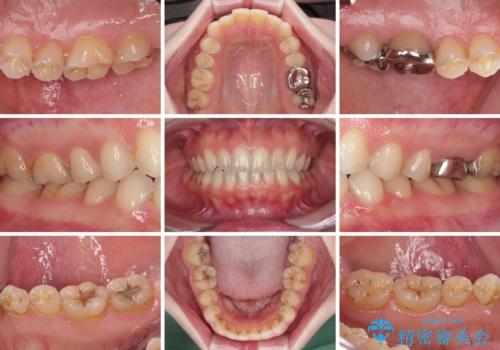

- 奥歯の銀歯をセラミックにしたいとのことで来院された患者様です。

当初は奥歯のみの治療をご希望でしたが、話を進めていくうちに、軽度ではあるものの、幼少期の薬の影響で歯が変色していることがコンプレックスであるということが分かりました。

長年歯の色が塞ぎ込んでいた部分があるとのことで、これを機会に全ての歯を真っ白にするために、オールセラミッククラウンにて補綴治療を行うこととしました。

より白さが目立つように、自然な仕上がりではなく、作り物の雰囲気があるフルジルコニアクラウンにて補綴治療を行いました。